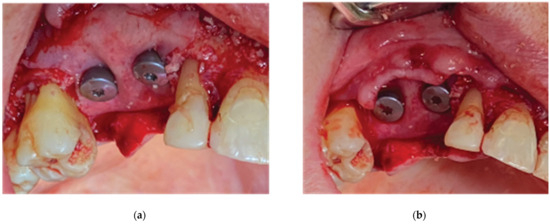

2.1. Case 1

- An initial stage for bone augmentation with simultaneous implant placement and emergence profile generation with the use of healing abutments (duration: from the beginning of treatment to complete implant osseointegration);

- A second stage for soft tissue management and cervical profile generation with the use of anatomical abutments (duration: from implant osseointegration to complete graft maturation).

2.2. Stage 1